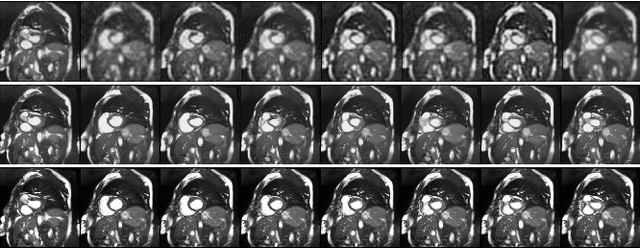

Super Resolution (SR) plays a critical role in computer vision, particularly in medical imaging, where hardware and acquisition time constraints often result in low spatial and temporal resolution. While diffusion models have been applied for both spatial and temporal SR, few studies have explored their use for joint spatial and temporal SR, particularly in medical imaging. In this work, we address this gap by proposing to use a Latent Diffusion Model (LDM) combined with a Vector Quantised GAN (VQGAN)-based encoder-decoder architecture for joint super resolution. We frame SR as an image denoising problem, focusing on improving both spatial and temporal resolution in medical images. Using the cardiac MRI dataset from the Data Science Bowl Cardiac Challenge, consisting of 2D cine images with a spatial resolution of 256x256 and 8-14 slices per time-step, we demonstrate the effectiveness of our approach. Our LDM model achieves Peak Signal to Noise Ratio (PSNR) of 30.37, Structural Similarity Index (SSIM) of 0.7580, and Learned Perceptual Image Patch Similarity (LPIPS) of 0.2756, outperforming simple baseline method by 5% in PSNR, 6.5% in SSIM, 39% in LPIPS. Our LDM model generates images with high fidelity and perceptual quality with 15 diffusion steps. These results suggest that LDMs hold promise for advancing super resolution in medical imaging, potentially enhancing diagnostic accuracy and patient outcomes. Code link is also shared.